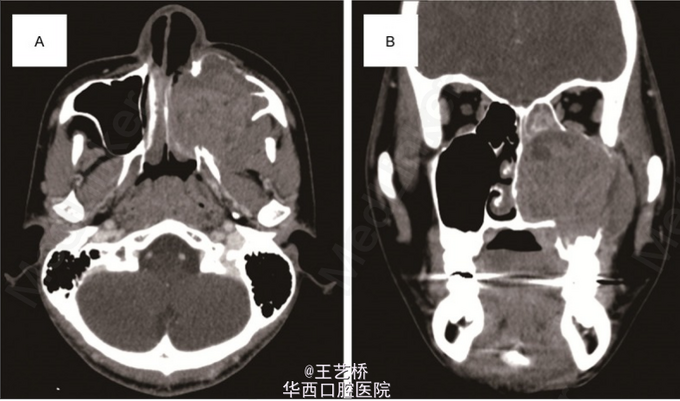

尤文肉瘤是小圆形细胞的低分化的恶性肿瘤,是儿童和青少年第二最常见的恶性骨肿瘤(仅次于骨肉瘤),在头颈部比较罕见,发生在上颌窦则更加少见了。病例中的15岁小男孩出现左侧面部肿胀,实验室检查无异常,进行CT检查时发现上颌窦出现密度影,周围骨质破坏。